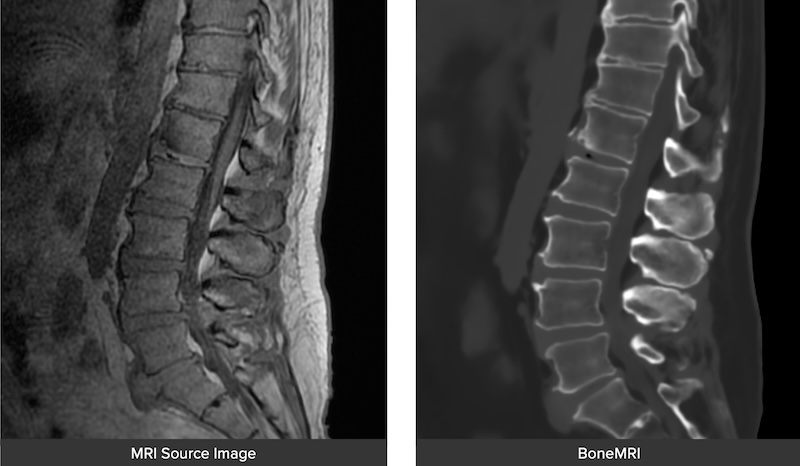

• MRIVision Module:

• Utilizes a specialized MRI sequence acquired preoperatively to produce a synthetic CT image which can be used to perform intraoperative FLASH for instant registration.

• Makes a completely radiation free process